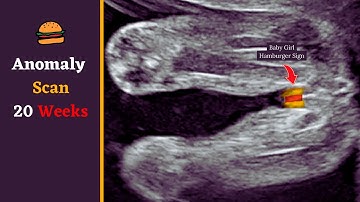

Scan 20